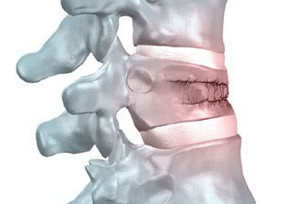

При компрессионном переломе страдает как раз тело позвонка. При этом сильная осевая нагрузка на отдел поясницы сочетается с резким сгибанием. Передние края позвоночных тел давят друг на друга, в результате чего костная ткань сжимается и разрушается. Если посмотреть на тело сломанного позвонка в продольном разрезе, то можно увидеть треугольник, клин. Вершина треугольника обращена кпереди, широкое основание кзади, то есть в просвет спинномозгового канала. Если повреждение очень сильное, сломанная часть способна дислоцироваться в сторону канала. Именно в этом и заключается главная опасность таких повреждений, так как может быть задет спинной мозг.